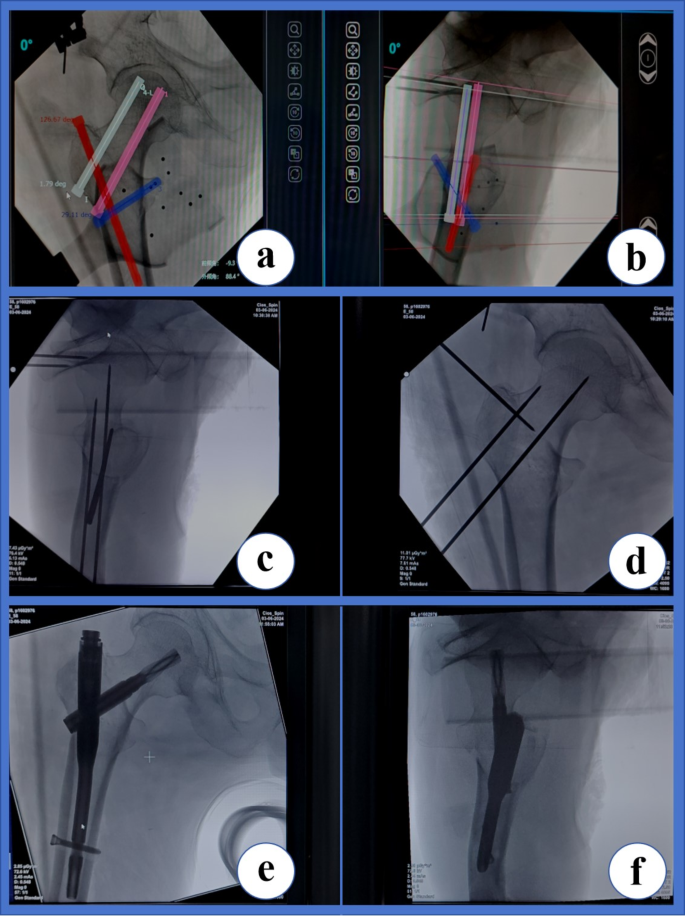

Step 4 was the activation and operation of the orthopedic robot (TiRobot, Tianzhihang Medical Technology) to complete PFNA surgery. Standard disinfection procedures were followed, and sterile drapes were used. The orthopedic surgical robot system was positioned, the machine was debugged and calibrated, and the C-arm machine was connected. After completion, fluoroscopy was performed to obtain anteroposterior and lateral images of the affected hip, which were subsequently transmitted to the robot workstation for four guide-pin placement planning. The general operation is detailed in reference7. The general operation was modified to include the planning of the placement and depth of the four guide pins (Fig. 1a, b). The 1st guide pin was used to temporarily fix both ends of the fracture to maintain stability and locate the femur calcar. The 2nd guide pin, if necessary, was used to fix the lesser trochanteric bone block and locate the posterior upper of the lesser trochanter. The 3rd guide pin was used to guide the drilling of the bone tunnel of the spiral blade and locate the femur calcar in the lower 1/3 of the femur neck. Finally, the 4th guide pin was used to guide the drill in drilling a hole at the insertion point for placement of the PFNA main nail at the apex and upper part of the greater trochanter of the femur. During the planning process, temporary fixation of the fracture ends and the lesser trochanter was necessary to avoid affecting the placement of the PFNA main nail. After the planning was completed, the robot machine arm was started, and the four guide pins (2.5 mm) were drilled into the bone in sequence under the guidance of the machine arm. After confirming that the positions of the guide pins were correct by fluoroscopy (Fig. 1c, d), the bone tunnel was predrilled with a hollow drill based on the position of the 3rd guide pin, which was temporarily withdrawn from the outer femoral cortex of the tunnel until the insertion of the main nail. Under the guidance of the 4th guide pin, the entry point in the greater trochanter of the femur was expanded into a hole by using a hollow drill. Next, guided by the 4th guide pin, a PFNA main nail was inserted at the hole in the proximal femur. When the hole in the spiral blade of the main nail overlapped with the predrilled bone tunnel of the spiral blade in a straight line, the 3rd guide pin was reinserted by hand, and the spiral blade was inserted and pressurized under guidance. Finally, under the guidance of the PFNA guide set, a distal screw was placed, the tail cap was installed, and the results were verified by fluoroscopy (Fig. 1e, f). After irrigation, the surgical incision was sutured.

Technical methods involving four guide pins by orthopedic robot-assisted PFNA surgery.(a, b), Planning the placement of the 1st guide pin (White) used to temporarily fix the fracture ends, planning the placement of the 2nd guide pin (blue) used to fix the lesser trochanter bone block, planning the placement of the 3rd guide pin (pink) used to guide the spiral blade, and planning the placement of the 4th guide pin (red) used to guide the main pin position. (c, d), With the assistance of the robot mechanical arm, these guide pins were placed under the guidance of anteroposterior and lateral fluoroscopy of the hip joint as needed. (e, f), Finally, under the guidance, PFNA was implanted and the results were verified by fluoroscopy.